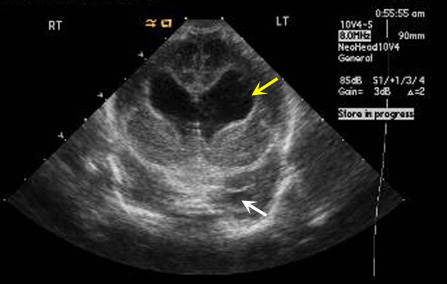

Infant with hydrocephalus

Case 3:

Imaging findings:

Figure 3. Ultrasound Head

Infant with hydrocephalus with dilatation of frontal horns of both lateral ventricles (yellow arrow) and temporal horn (white arrow).